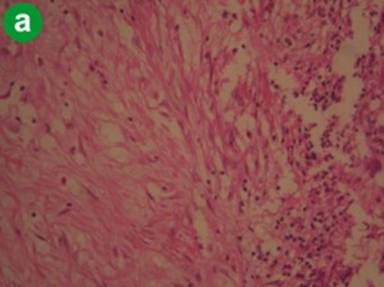

Tropical Calcific Pancreatitis

H&E staining showed atrophic acini and increased stromal component consistently in all the specimens and also prominent dilated ducts and mononuclear inflammatory cell infiltrates (Figure 1a). Immunohistochemistry with α-SMA showed dense and diffuse staining pattern in areas of fibrosis. Periacinar and periductal staining was noted. Positive staining was also present in the wall of vessels and ducts (Figure 1b). Staining with CD34 showed no or sparse positivity in the areas of fibrosis, but stained areas were observed in smooth muscle components of blood vessels and ducts (Figure 1c). These observations suggest that activated stellate cells are extensively present in the areas of fibrosis. The diffuse staining pattern represents the elongated cytoplasmic processes of PSCs extending extensively in the fibrotic areas and also into the periacinar spaces. However, the extent of staining was variable from patient to patient and only sparse staining was present in some cases.

Figure 1. Representative staining pattern observed in cases tropical calcific pancreatitis (a. H&E, b. α-SMA, c. CD34). |